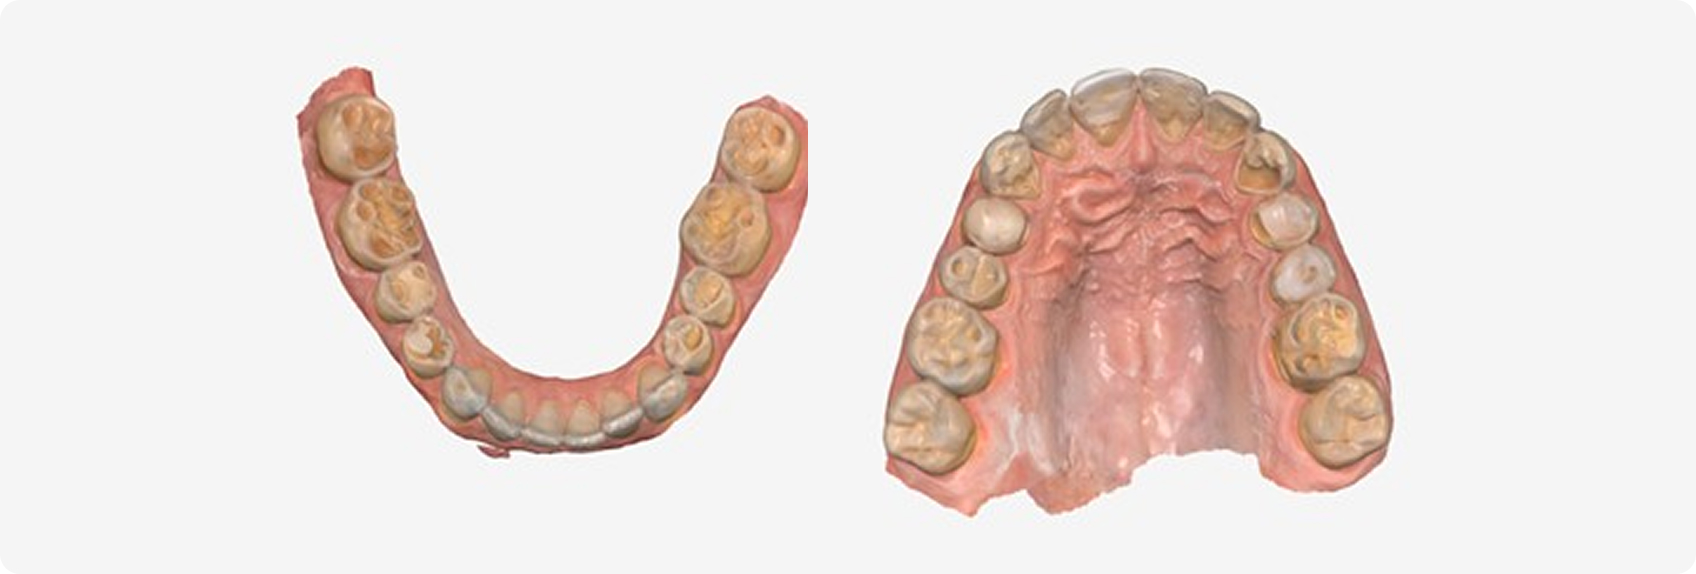

Robert, age 34, presented with severe wear, GERD, and mild obstructive sleep apnea (Fig. 8). Two practices recommended full-mouth reconstruction, but financial barriers prevented treatment.

Clinical and radiographic evaluation revealed multifactorial wear, including erosive and attritional components. Medical history was significant for gastroesophageal reflux disease (GERD) and obstructive sleep apnea (OSA), with an apnea-hypopnea index of 7.5.

Digital scans were used to create a diagnostic wax-up and design posterior resin onlays (Fig. 9). Teeth were air-abraded to enhance adhesion, and onlays were bonded without tooth preparation.